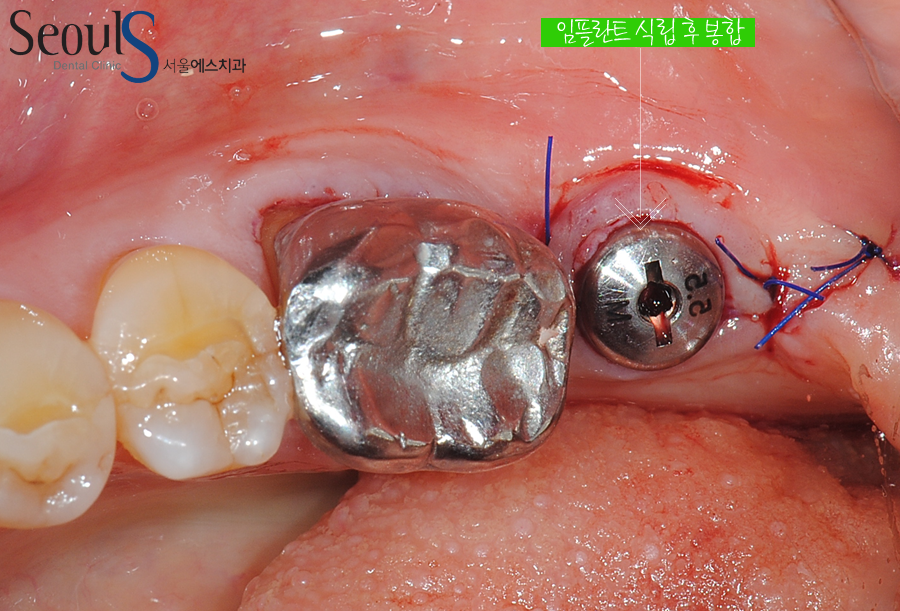

맨 끝 어금니가 빠져서 임플란트를 식립했습니다

임플란트 식립 후 잇몸을 봉합한 모습으로 임플란트가 잇몸 밖으로 노출된 모습입니다

임플란트를 식립할 때 식립 후 잇몸 밖으로 노출시키는 경우가 있고

잇몸으로 임플란트를 덮는 경우가 있습니다

잇몸뼈 상태에 따라 임플란트를 노출하거나 잇몸으로 덮게 되는 것으로

잇몸뼈가 튼튼해 임플란트가 잇몸뼈에 단단히 결합된 경우

임플란트가 움직일 염려 없어 잇몸 밖으로 노출시키고

잇몸뼈가 부족해 뼈이식을 한 경우  임플란트가 잇몸뼈와 굳는 과정에서 움직일 염려가 있기 때문에 잇몸으로 임플란트를

덮어 임플란트가 움직이는 것을 방지하게 됩니다